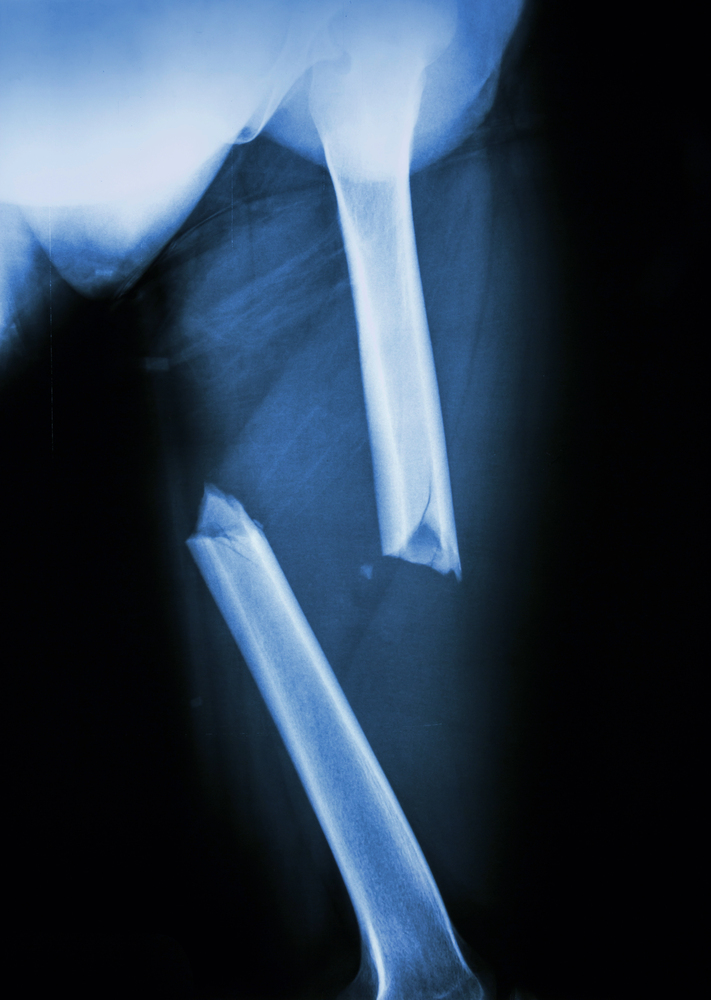

Furthermore, there are several types of femur fractures, some of which are more severe than others:

- Transverse fracture – The force broke the femur straight across the femur shaft in a horizontal line.

- Comminuted fracture – In this case, the bone has broken into three or more pieces.

- Oblique fracture – The femur break is an angled line across the shaft.

- Spiral fracture – Spiral fractures encircle the shaft. This break often happens when the leg is twisted.

- Open fracture – An open or compound fracture involves broken bone fragments sticking through the skin. In other cases, the wound is so deep that it reveals the bone. This type of femoral shaft fracture will most likely lead to complications, especially infections.